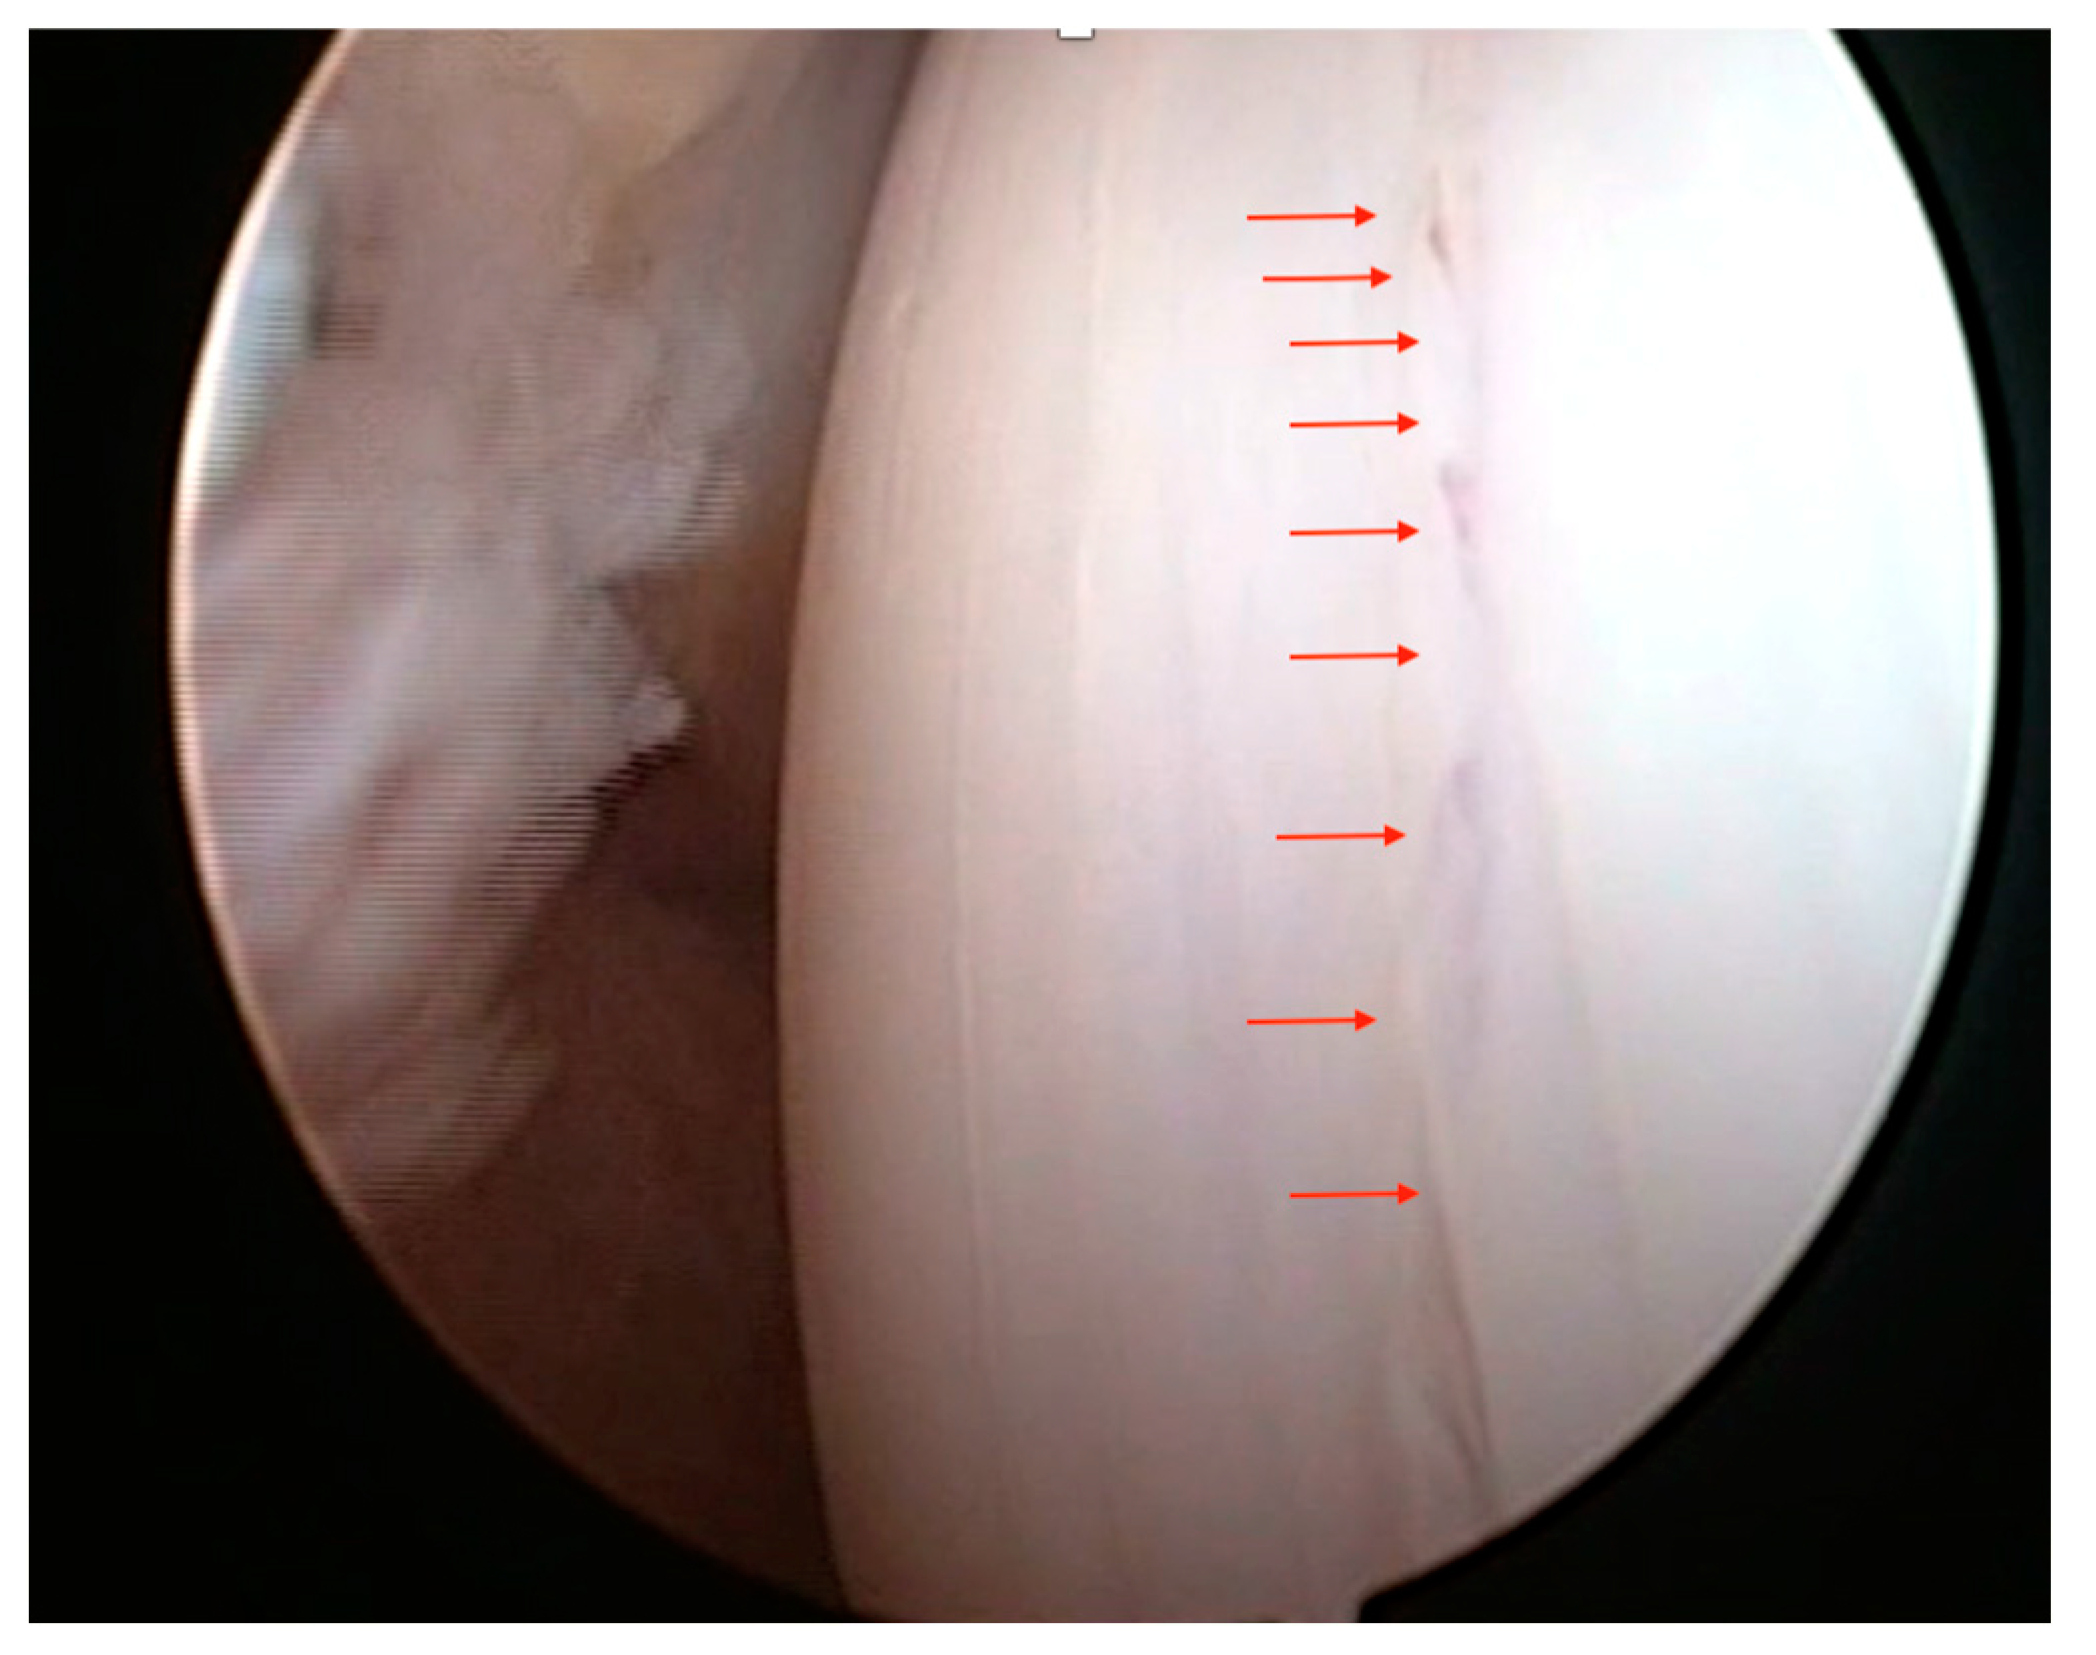

- Wear lines on the articular surface (Figure 10)